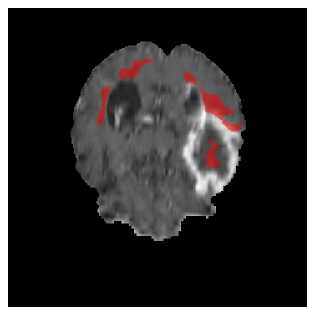

Appendix A Qualitative results

Figure 5 illustrates the segmentation evolution for the same BRATS patient in S2 sequence. The key difference here is that the best buffer-free strategy is EWC (=1), and training on BRATS data starts from episode 2 instead of episode 1 as BRATS is encountered at episode 2 in S2. The cumulative approach retains segmentation across episodes but continues to generate false positives, which become even more pronounced in the final episode. The naive approach, lacking a CL mechanisms, completely overrides previous knowledge, leading to failed segmentation in later episodes. EWC (=1) approach initially maintains segmentation but experiences a sharp decline in episode 4, where it fails to segment the tumor. In the final episode, it undersegments the lesion, missing a significant portion of the tumor. In contrast, the proposed approach consistently preserves segmentation across episodes. While initially introducing false positives, it gradually refines predictions, retaining the tumor region while minimizing misclassifications. It maintains clear tumor delineation by the final episode, demonstrating effective knowledge retention and adaptability throughout training.